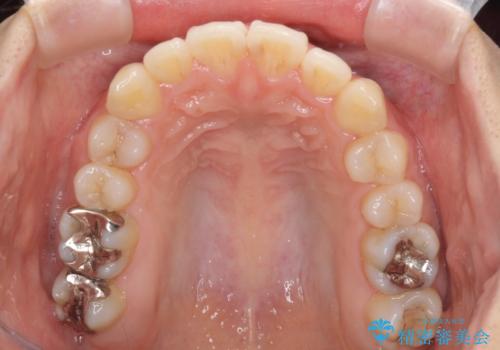

前歯の突出感とデコボコ インビザラインで改善

- 上下前歯のデコボコを気にして来院された患者様です。

インビザラインによる上下歯列の側方拡大と後方移動、IPR(歯と歯の間を削る)にるスペースの獲得により歯列を整えることとしました。

右上の小臼歯は歯根癒着をしており、様々な方法を試みるも動かすことができませんでした。

それでも奥歯のかみ合わせに不自由はなく、歯列をきれいに整えることができました。